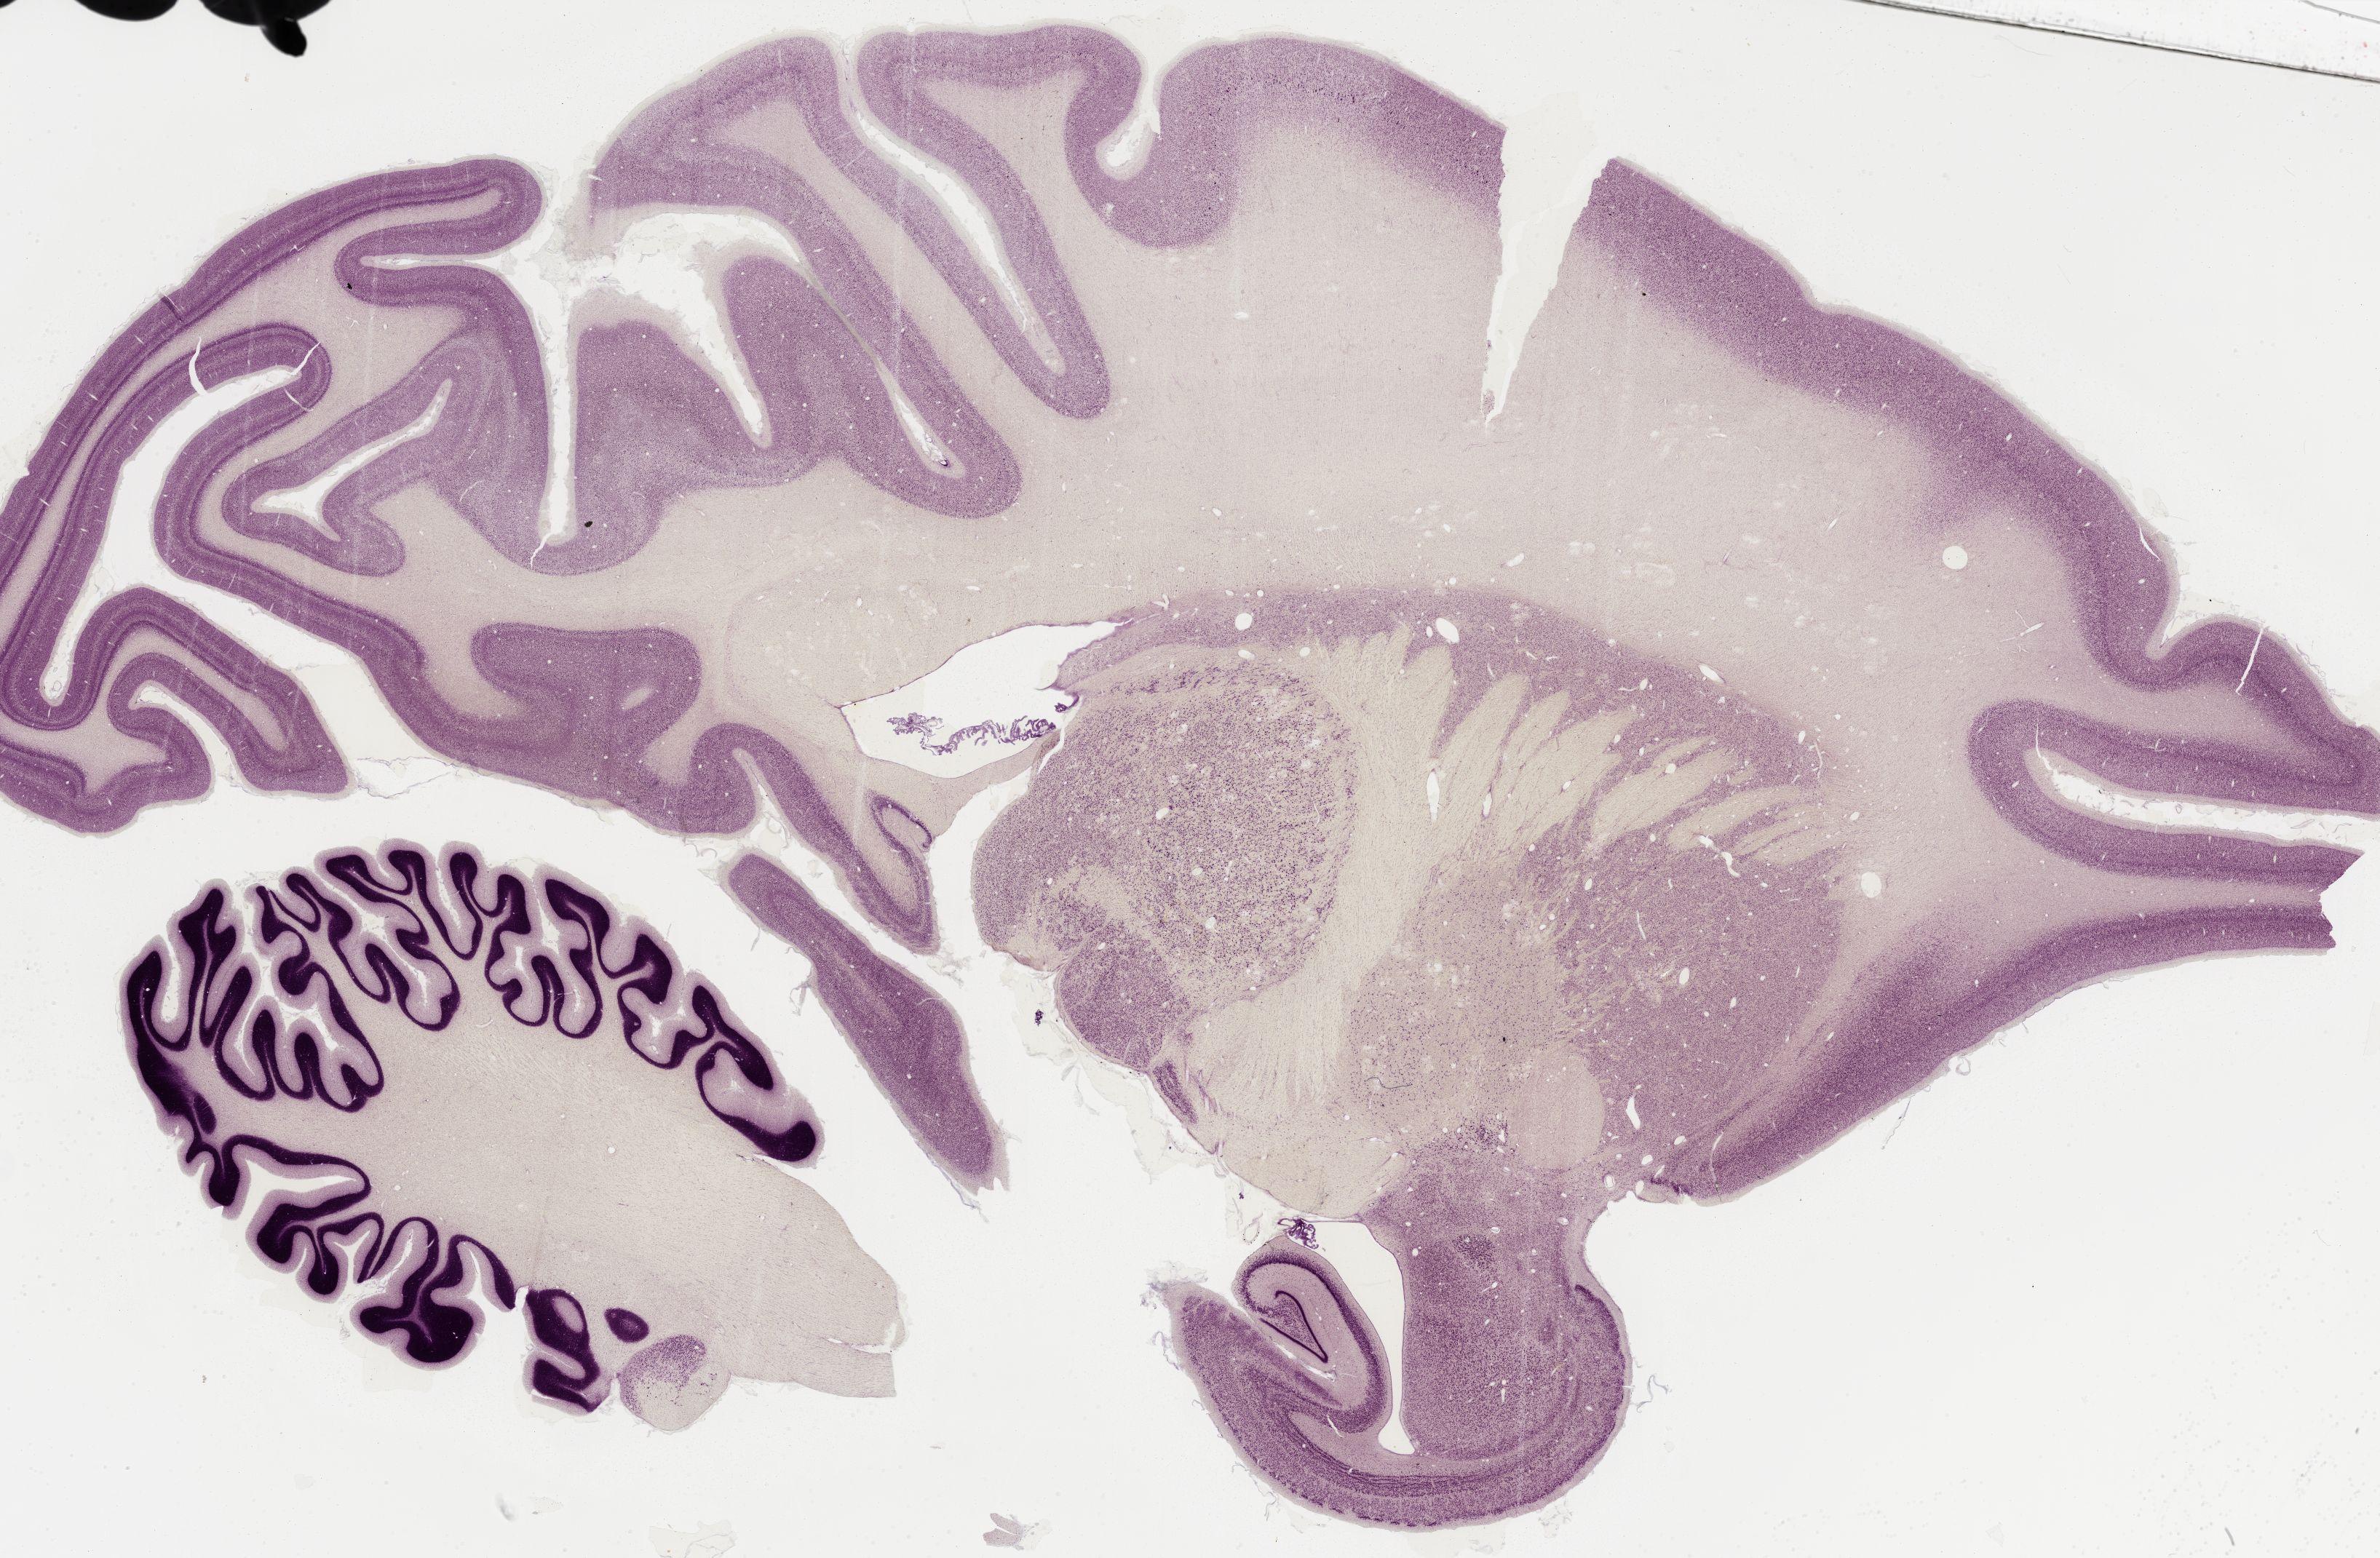

Datasets -> Macaca Mulatta -> Nissl, sagittal, histo, Whole-Brain, adult

[ Metadata ]   ·   Source: Edward G. Jones

Displaying Sections 161 thru 200 of 295 Sections for this Dataset

0364 - labeled